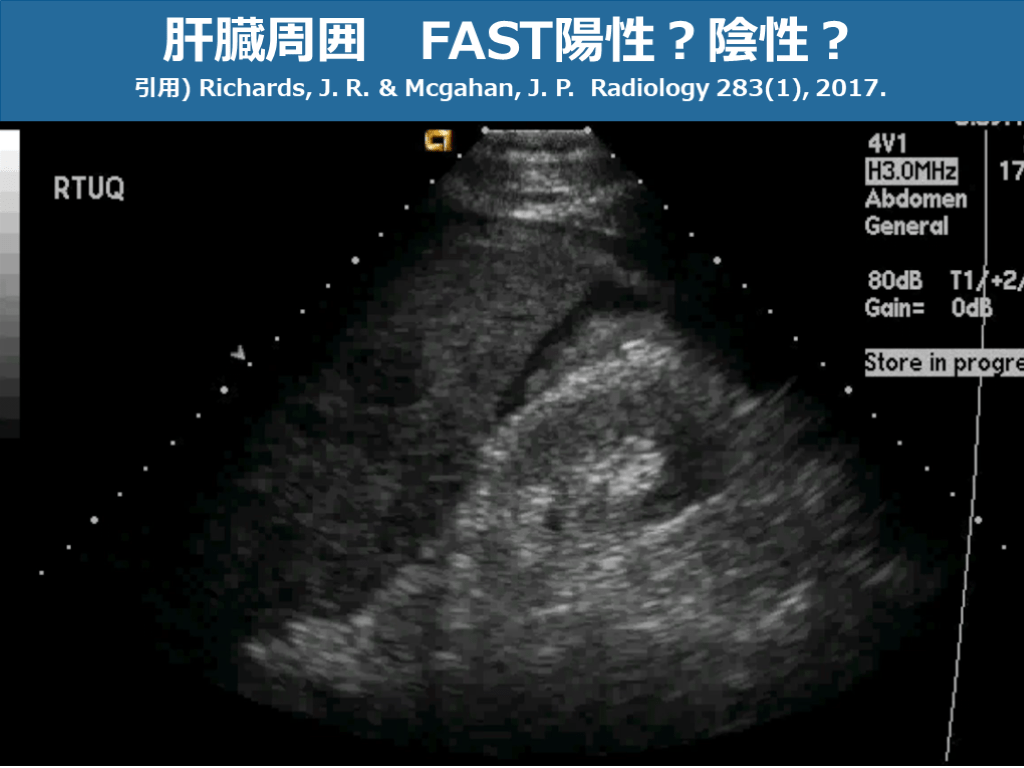

肝臓周囲 FAST陽性?陰性? 引用) Richards, J. R. & Mcgahan, J. P. Radiology 283(1), 2017. スライド画像)広島大学病院 演者作成

肝臓周囲 FAST陽性?陰性? 引用) Richards, J. R. & Mcgahan, J. P. Radiology 283(1), 2017. スライド画像)広島大学病院 演者作成 モリソン窩少量EFSあり